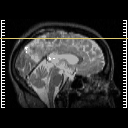

Click on sagittal image to select slice. Click on thin tickmark to change timepoint, or thick tickmark for overlay.